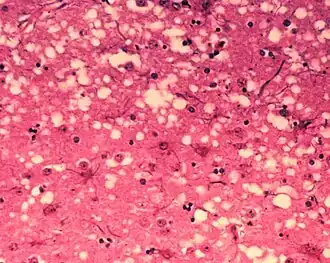

Diagnosis of BSE continues to be a practical problem. It has an incubation period of months to years, during which no signs are noticed, though the pathway of converting the normal brain prion protein (PrP) into the toxic, disease-related PrPSc form has started. At present, no way is known to detect PrPSc reliably except by examining post mortem brain tissue using neuropathological and immunohistochemical methods. Accumulation of the abnormally folded PrPSc form of PrP is a characteristic of the disease, but it is present at very low levels in easily accessible body fluids such as blood or urine. Researchers have tried to develop methods to measure PrPSc, but no methods for use in materials such as blood have been accepted fully.

The traditional method of diagnosis relies on histopathological examination of the medulla oblongata of the brain, and other tissues, post mortem. Immunohistochemistry can be used to demonstrate prion protein accumulation.[26]

BSE prions are misfolded forms of the particular brain protein called prion protein. When this protein is misfolded, the normal alpha-helical structure is converted into a beta sheet. The prion induces normally-folded proteins to take on the misfolded phenotype in an exponential cascade. These sheets form small chains which aggregate and cause cell death. Massive cell death forms lesions in the brain which lead to degeneration of physical and mental abilities and ultimately death.[15] The prion is not destroyed even if the beef or material containing it is cooked or heat-treated under normal conditions and pressures.[16] Transmission can occur when healthy animals come in contact with tainted tissues from others with the disease, generally when their food source contains tainted meat.[2]